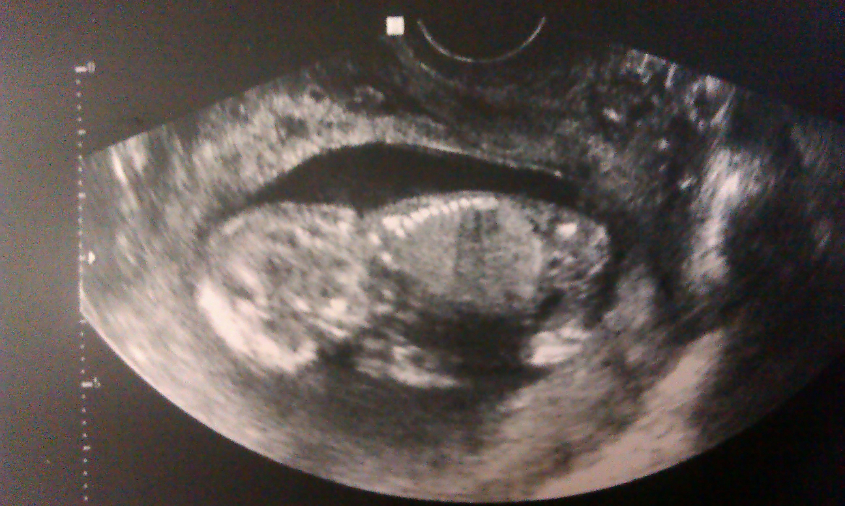

Тааааа-дам! И мой лимончик, лежит к нам спиной, редко поддергивая ножками. Улыбка! Счастье и радость меня расперало.))))

На каждом повороте датчика УЗИ, врач комментировала "Ой а какие мы красивые! А у нас и тут все хорошо" И малыш начал активно махать ручками и ножками, крутиться вокруг своей оси, как рыбка. Я даже перепугалась, но сказали все нормально, так и должно быть. Слова очень успокаивали, я смотрела на монитор не отрываясь. Вторая волна радости меня на крыла снова, когда врач долго рассматривала что-то и сказала "Я уверена больше чем на 70%, что у тебя будет мальчик" Говорит, что разгледела начало 'достоинства' ))Впервые я видела крошку в 7 недель, где КТР было 8мм, а сейсас мы уже большие КТР 69мм. ЧСС 151уд/мин. По сроку у нас 12 нед и 1день, а по УЗИ нам поставили 13 недель ровно. Сказали, что богатырь растет)))

А ВОТ И МЫ!